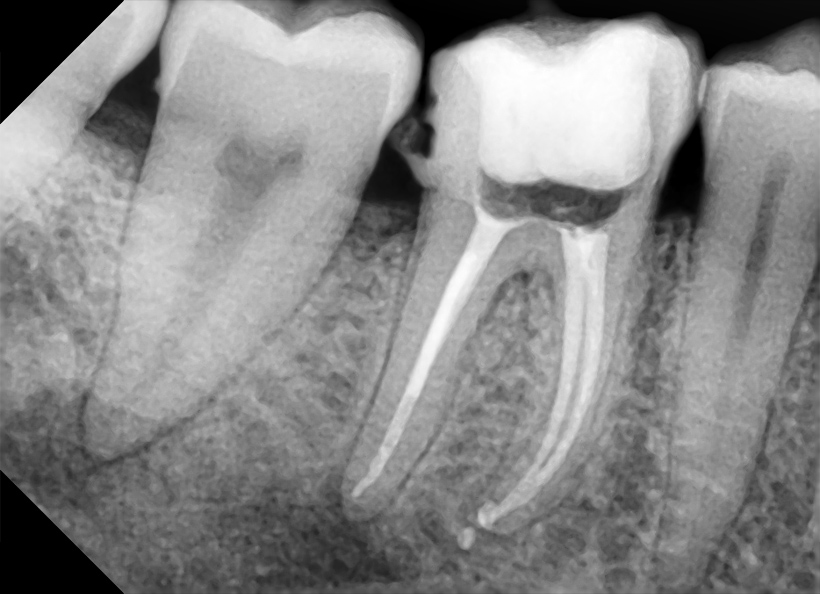

Radiografia digitală retroalveolară dentară este o radiografie digitală care se realizează la unul, maxim doi dinţi. Această radiografie permite medicului stomatolog să vadă în detaliu coroana şi rădăcina întregului dinte, la dimensiuni reale. De obicei această radiografie este indicată când se face un tratament endodontic (se scoate nervul) sau pentru o rezecţie apicală (operaţia rădăcinii dintelui).